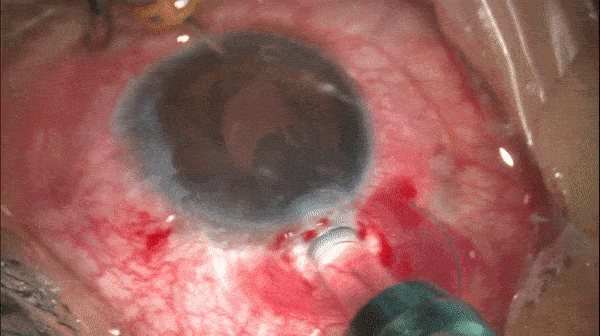

Step 10

无瓣膜巩膜缝线固定对侧攀

对侧攀重复步骤8和步骤9的操作。(图示完成后)

开睑器怎么用术说睛彩 | 金海鹰教授:使用8-0缝线的无巩膜瓣人工晶体固定手术_https://www.jmylbn.com_新闻资讯_第13张